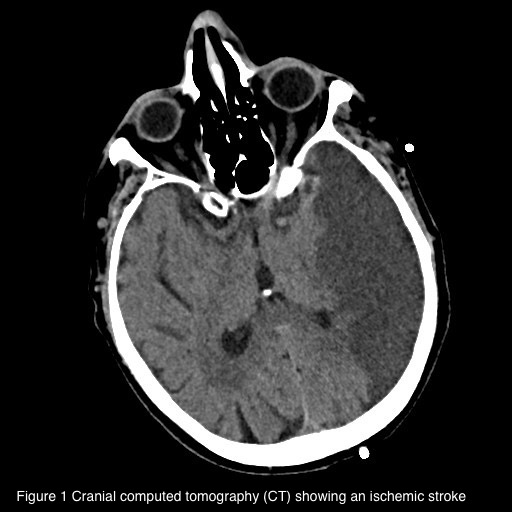

Introduction Ischemic stroke (IS) is caused by the obstruction of cerebral blood vessels, resulting in reduced blood flow and impaired oxygen delivery. It can be caused by atherothrombotic occlusion of large arteries, cerebral embolism or non-thrombotic occlusion of small, deep cerebral arteries. Cardioembolic IS can occur in the presence of various cardiac conditions, such as cardiac masses, patent foramen ovale (PFO), endoluminal thrombosis and sometimes as complication of infective endocarditis (IE). We present the case of a patient admitted to Intensive Care Unit (ICU) after non-cardiac surgery (NCS) who developed IS with high suspicioun of cardioembolic origin. Case presentation A 67-year-old man admitted to ICU developed right-sided hemiparesis after laparoscopic enterolysis surgery. His past medical history included a previous intestinal resection for ischemia. Computed tomography (CT) confirmed IS (1) , suspicious for embolic origin. Atherosclerosis of large cerebral vessels was excluded. Due to post-operative fever, blood cultures were collected and an infection caused by S. Aureus and M. Morganii was detected. Transoesophageal echocardiogram (TEE) was performed to confirm the suspicion of IE with embolization. TEE showed PFO with a significant right–to-left shunt (2B) . Moreover, a floating thrombus was detected in the pulmonary artery (2A) . No IE was found. CT angiography confirmed pulmonary thromboembolism (PE) (3) . Unfortunately, the patient died because of post-operative complications. Discussion The peculiarity of this case is represented by the unexpected aetiology of IS considering the clinical confounding presentation. At first, the most probable expected cause was represented by IE but PE and paradoxical embolization due to large PFO turned out to be responsible of IS. Some studies demonstrate PFO association with increased risk of IS in patients undergoing NCS in different settings. The prevalense of PFO in the general population is estimated at approximately 20-25% but the lack of a systematic screening in patients without IS likely underestimates its prevalence. Currently, PFO closure in addition to anti-aggregation therapy is indicated in patients with IS when a strong causal relationship between PFO and stroke is demonstrated. Further prospective trials are needed to identify a specific population at risk of perioperative IS associated with PFO in order to define systematic screening, prevention plans and improve perioperative outcomes.